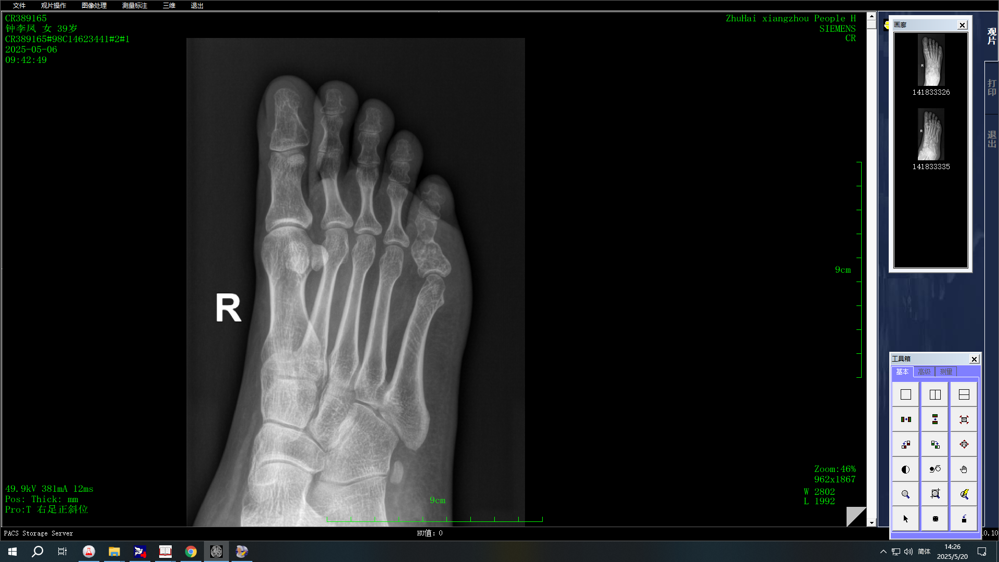

术前影像学检查

近日,骨科门诊接诊了一位患者,他因足趾轻微外伤而疼痛难忍。患者自述只是轻轻碰了一下,便出现了剧烈疼痛。经进行X线及磁共振检查后,却发现患者确实发生了骨折,而且是病理骨折。影像学检查提示患者的足趾患有“内生软骨瘤”,正是由于这个肿瘤导致骨质强度下降,才导致了此次骨折。

(一)X线(首选方法)检查典型表现为:

1.边界清晰的椭圆形或分叶状透亮区(低密度影);

2.内部可见点状、环状钙化(“爆米花样”或“云雾状”特征);

3.骨皮质完整,无软组织侵犯。